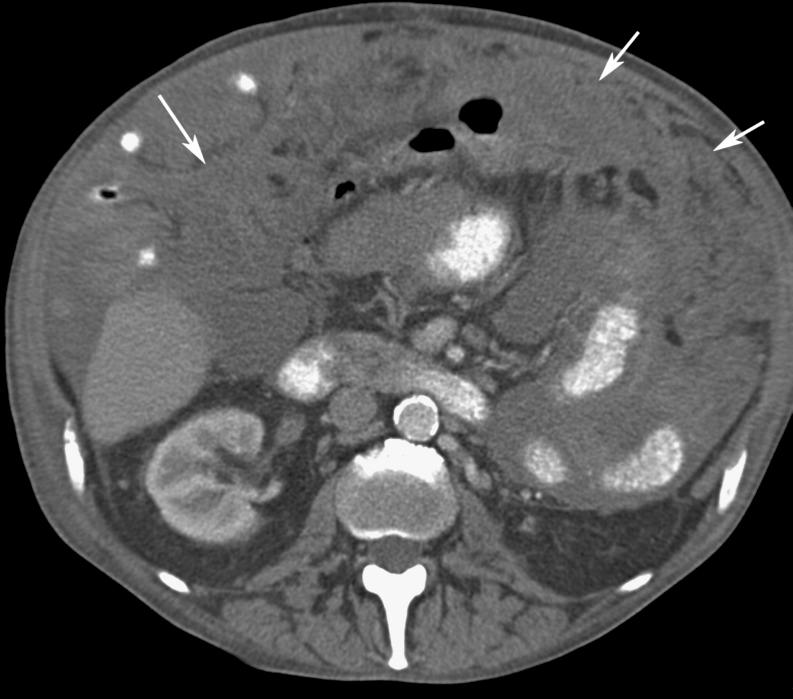

Omental cakes typically are associated with ovarian carcinoma, as this is the most common malignant aetiology. Nonetheless, numerous other neoplasms, as well as infectious and benign processes, can produce omental cakes. METHODS: A broader knowledge of the various causes of omental cakes is valuable diagnostically and to direct appropriate clinical management. RESULTS: We present a spectrum of both common and unusual aetiologies that demonstrate the variable computed tomographic appearances of omental cakes. CONCLUSION: The anatomy and embryology are discussed, as well as the importance of biopsy when the aetiology of omental cakes is uncertain.